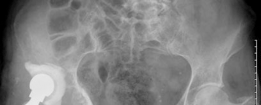

- Standard Radiographs: Anteroposterior (AP) pelvis, frog-leg lateral, and a true lateral of the affected hip are essential. These provide initial assessment of component position, subsidence, osteolysis, and general bone architecture. Stress views may be helpful for suspected pelvic discontinuity.

- This image could be a post-operative radiograph showcasing the completed reconstruction with an augment and revision cup. -

- Another post-operative X-ray providing a different view or illustrating a similar case. -

- A close-up radiographic view highlighting the augment and its screw fixation, along with the acetabular cup. -

- An example of a particularly complex reconstruction, potentially involving a larger augment or cage. -

- A final illustrative image, possibly demonstrating long-term follow-up or a specific technical detail.